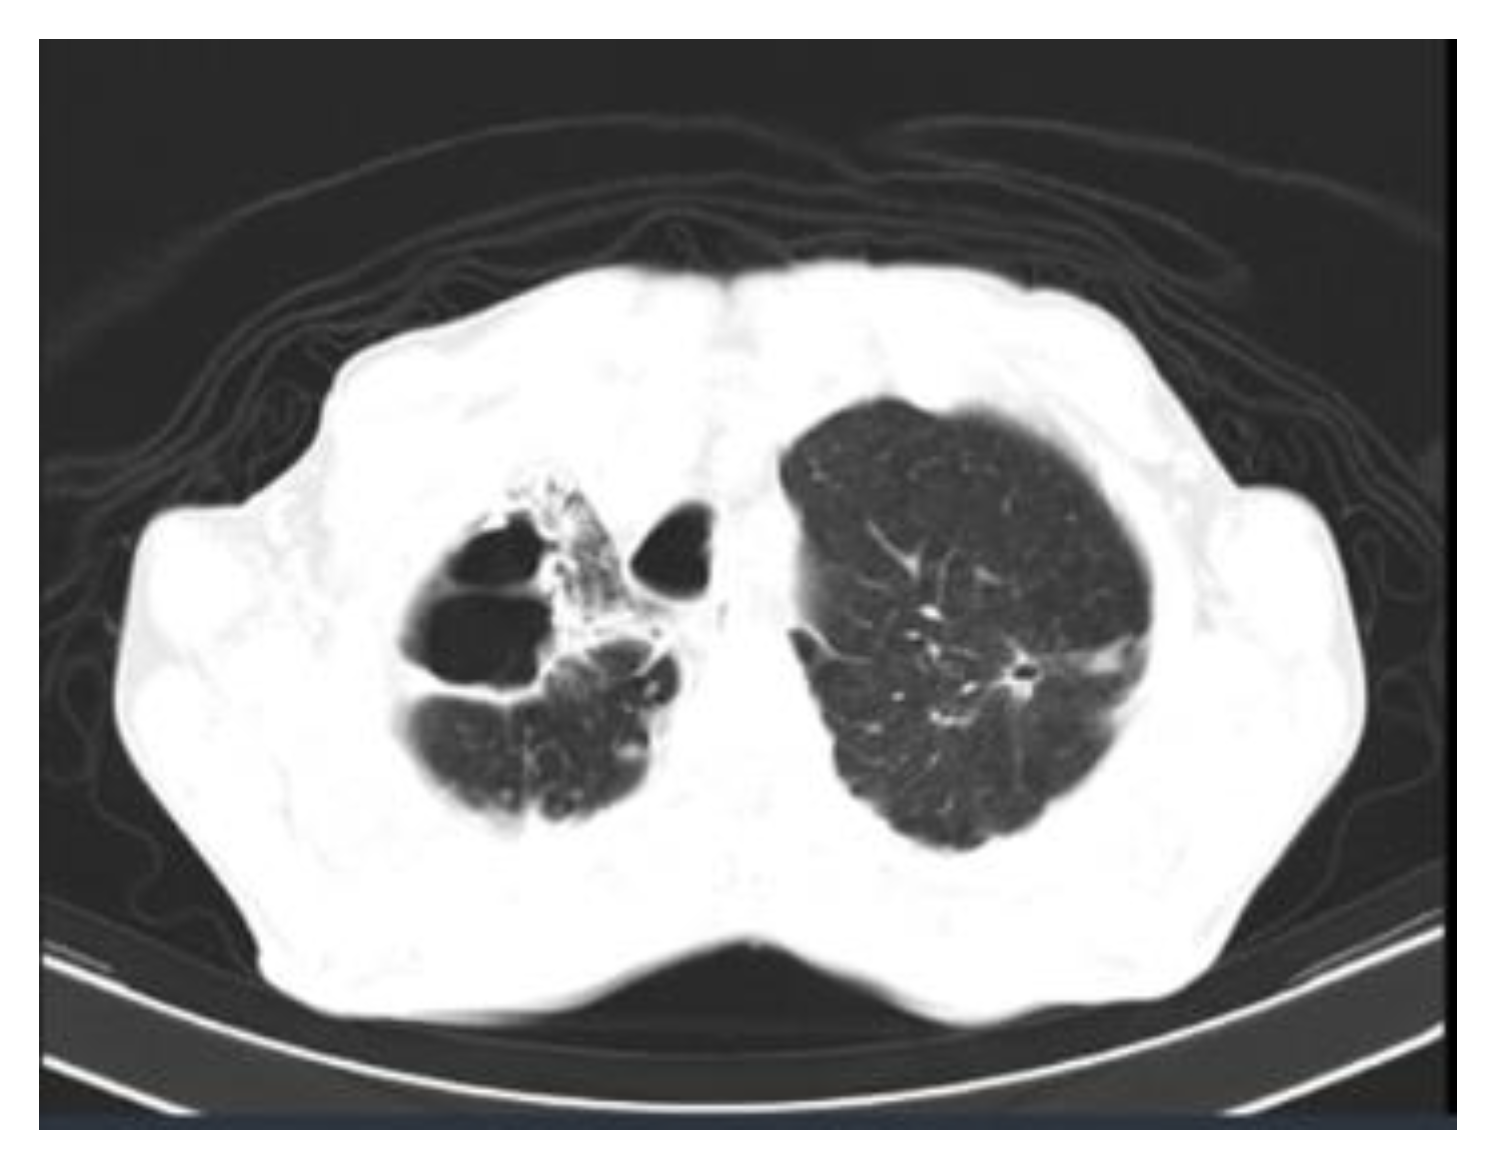

- Fichman, V.; Mota-Damasceno, C.G.; Procópio-Azevedo, A.C.; Almeida-Silva, F.; de Macedo, P.M.; Medeiros, D.M.; Astacio, G.S.; Zancopé-Oliveira, R.M.; Almeida-Paes, R.; Freitas, D.F.S.; et al. Pulmonary Sporotrichosis Caused by Sporothrix brasiliensis: A 22-Year, Single-Center, Retrospective Cohort Study. J. Fungi 2022, 8, 536. [Google Scholar] [CrossRef]

- Aung, A.K.; Spelman, D.W.; Thompson, P.J. Pulmonary Sporotrichosis: An Evolving Clinical Paradigm. Semin. Respir. Crit. Care Med. 2015, 36, 756–766. [Google Scholar] [CrossRef]

| Lungs | 3 (0.3) | |

| pulmonary | 2 | |

| primary pulmonary sporotrichosis + wrist synovitis | 1 | |